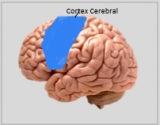

Neuroanatomie is de tak van de anatomie die de anatomie van het zenuwstelsel bestudeert, dat wil zeggen de structuur, functie en organisatie van het zenuwstelsel. Het zenuwstelsel is een van de meest complexe systemen in het menselijk lichaam en omvat de hersenen, het ruggenmerg, perifere zenuwen en zenuwganglia. Neuroanatomie houdt zich bezig met hoe deze structuren met elkaar verbonden zijn, hoe signalen tussen zenuwcellen worden doorgegeven en hoe de verschillende delen van het zenuwstelsel samenwerken om lichamelijke en cognitieve functies te besturen. Neuroanatomen maken gebruik van geavanceerde beeldvormingstechnieken, zoals MRI (magnetic resonance imaging), PET (positron emission tomography) en microscopie om de structuren en functies van het zenuwstelsel te visualiseren.